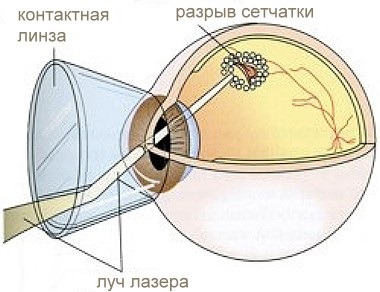

lentile de contact Fundus sunt proiectate pentru larg câmp de studiu fundus stereoscopice de biomicroophthalmoscopy, precum și pentru chirurgie cu laser pe membrane și structuri ale ochiului intern.

Fig. 1 și 2 (lentilă Fundus).

Pe lângă sarcinile obschediagnosticheskih lentilele fundus sunt proiectate pentru a efectua intervenții cu laser în fundus, în special pentru coagularea retinei panretinal. Acestea pot fi utilizate pentru a efectua coagularea distrofii periferice, tromboză vasculară retiniană și altele.

Metode de utilizare a fundului de ochi a cristalinului atunci când coagulează operatie cu laser pe retină nu este fundamental diferită de cealaltă. Cunoscută Cu toate acestea, datorită câmpului vizual mare și în mod corespunzător o creștere mică a imaginii observate, coagulează, chiar și diametrul mediu (200-300 microni) să pară mai mică (valoarea reală a acestora de 1,5 ori mai mare).